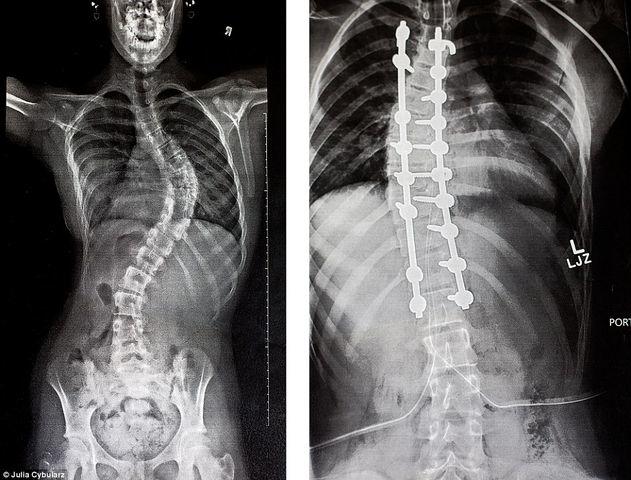

Cột sống của Tiểu Văn đã cong 60 độ (Ảnh minh họa)

Đợi đến hơn 1 năm, khi Tiểu Văn thuận lợi vượt qua bài thi chuyển cấp, mẹ mới nghĩ đến việc đưa con gái đến bệnh viện khám, nhưng tiếc là lúc này xương cột sống của Tiểu Văn đã thành hình chữ S, sau khi đo thì cột sống cong 60 độ, thuộc vào loại biến dạng nghiêm trọng, cần phải phẫu thuật điểu trị.